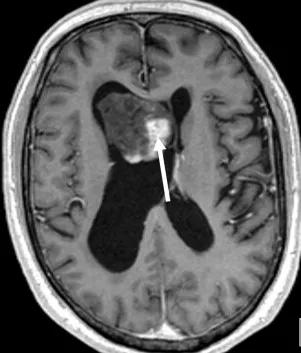

Κεντρικό νευροκύτωμα (WHO II)

Τυπικά εμφανίζεται σε νεαρούς ενήλικες, με εντόπιση κοντά στο ενδοκοιλιακό τρήμα του Monro και κλινική εικόνα αυξημένης ενδοκράνιας πίεσης.

Το κεντρικό νευροκύτωμα είναι σπάνιος όγκος (κάτω από 1% των ενδοκράνιων μαζών) και είναι συχνότερο στην 2η με 4η δεκαετία. Συχνά εντοπίζεται κοντά στο ενδοκοιλιακό τρήμα του Monro ή εντός της 3ης κοιλίας. Στην CT εγκεφάλου μπορεί να είναι υπέρπυκνο με στικτές επασβεστώσεις. Στην MRI έχει συνήθως ετερογενή ενίσχυση μετά ενδοφλέβια χορήγηση σκιαγραφικού και εμφανίζει μικρές κυστικές περιοχές.

Η πλήρης χειρουργική αφαίρεση της βλάβης είναι συνήθως θεραπευτική. Στην Neuroknife, η ριζική εξαίρεση συνδυάζεται πάντοτε με προσεκτικό σεβασμό των παρακείμενων νευρικών δομών και της φλεβικής παροχέτευσης των κοιλιών.